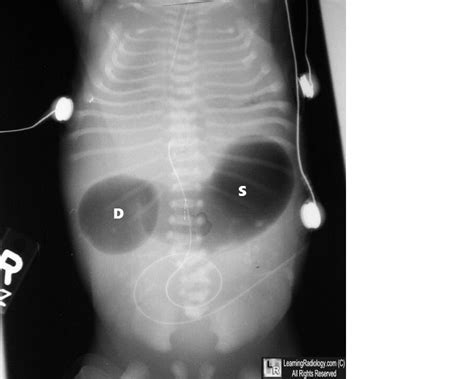

Double Bubble Sign X Ray. The double bubble sign is an ultrasonographic finding that commonly represents duodenal atresia and is associated with trisomy 21. Single bubble sign in congenital.

This test looks for air or fluid in the stomach and first part of the intestine. Web a double bleb sign is a sonographic feature where there is visualization of a gestational sac containing a yolk sac and amniotic sac giving an appearance of two small. A picture mostly related to duodenal atresia. Classically, for duodenal atresia, one will see an enlarged (dilated) stomach and. The double bubble sign is an ultrasonographic finding that commonly represents duodenal atresia and is associated with trisomy 21. Little to no air is in. Web 1) osophageal atresia, 2) pyloric stenosis, 3) duodenal atresia, 4) colonic atresia, 5) null Web the triple bubble sign is the classic radiographic appearance observed in jejunal atresia 1,2. Frontal double bubble sign with no gasses in the distal bowel. Single bubble sign in congenital.